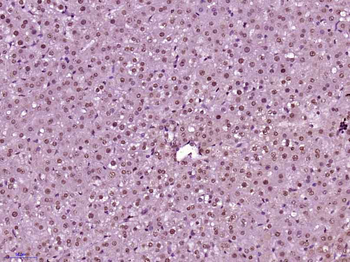

CDKN1A Antibody

Catalog Number: orb682382

| Description | CDKN1A Antibody |

| Target | CDKN1A |